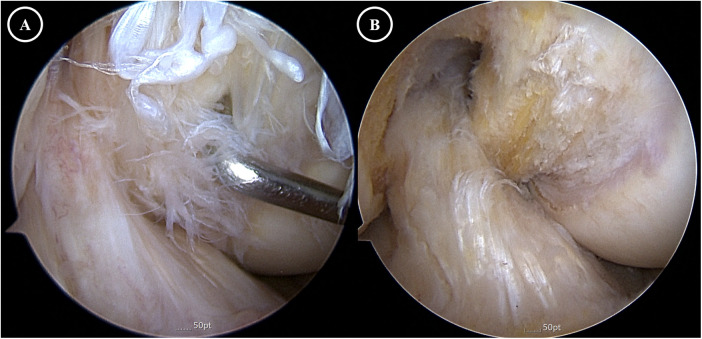

交叉韧带的黏液变性是一种罕见且常被忽视的慢性膝关节疼痛和运动受限的原因。我们报告的情况下,62岁的男子有8年的历史不适,进行性屈曲挛缩,并限制活动范围在右膝。之前在其他地方进行的两次关节镜检查未能确定原因。磁共振成像采用1.5-Tesla扫描仪,切片厚度为3mm,显示前、后交叉韧带弥漫性,韧带内信号增加,纤维完整,与“芹菜茎”征一致。关节镜检查通过标准的前外侧和前内侧门显示两个十字韧带肥大,淡黄色组织。每个韧带大约50%的体积被切除,保留了剩余的完整纤维以保持稳定性。组织学检查证实粘液变性,无炎症浸润。术后6个月,患者实现完全伸展,屈曲度提高至130°,疼痛完全缓解,无临床不稳定。本病例强调了在排除常见关节内病变的情况下,将同时发生的前交叉韧带和前交叉韧带黏液变性作为难愈性膝关节僵硬患者的潜在诊断的重要性。

Mucoid degeneration of the cruciate ligaments is an uncommon and often under-recognized cause of chronic knee pain and motion limitation. We report the case of a 62-year-old man with an eight-year history of discomfort, progressive flexion contracture, and restricted range of motion in the right knee. Two prior arthroscopies performed elsewhere failed to identify the cause. Magnetic resonance imaging using a 1.5-Tesla scanner with 3-mm slice thickness demonstrated diffuse, increased intraligamentous signal with intact fibers in both the anterior and posterior cruciate ligaments, consistent with the "celery stalk" sign. Arthroscopy through standard anterolateral and anteromedial portals revealed hypertrophic, yellowish ligament tissue in both cruciates. Approximately 50% of the bulk of each ligament was resected with preservation of the remaining intact fibers to maintain stability. Histologic examination confirmed mucoid degeneration without inflammatory infiltration. At six months postoperatively, the patient achieved full extension, improved flexion to 130°, and complete resolution of pain, without clinical instability. This case emphasizes the importance of considering simultaneous ACL and PCL mucoid degeneration as a potential diagnosis in patients with refractory knee stiffness when common intra-articular pathologies have been excluded.